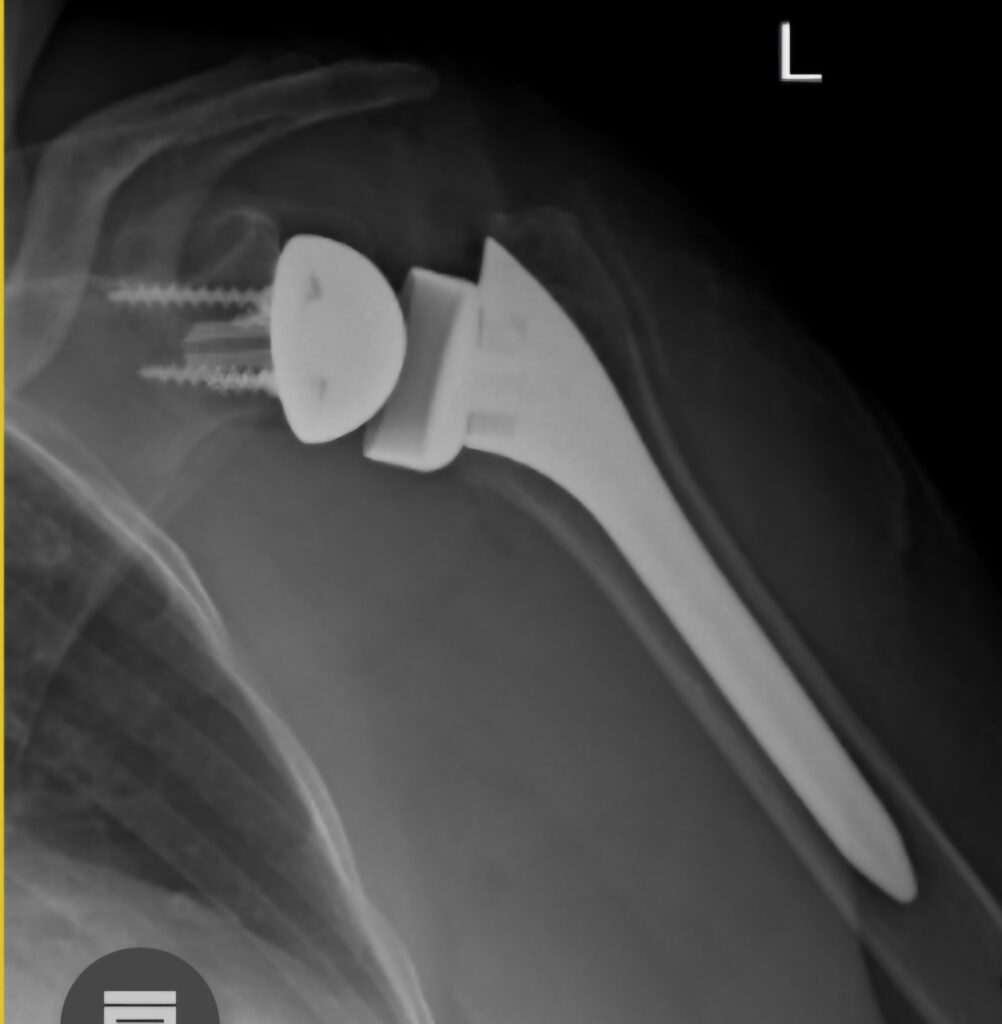

REVERSE TOTAL SHOULDER REPLACEMENT

The rotator cuff is responsible for centering the humeral head in the glenoid and to initiate movement of the shoulder. After initiation the movement is powered by large muscles like the Deltoid and the Pec major etc. If the cuff is torn the first prize is a proper repair , but in patients older than 75 the outcomes are poor. In this patient group there is an alternative, namely a reverse total shoulder replacement. By reversing the ball and socket from the anatomical arrangement, the Deltoid muscle is able to initiate and complete motion of the shoulder. This is and excellent answer to a sticky problem. Not a good option for young patients though